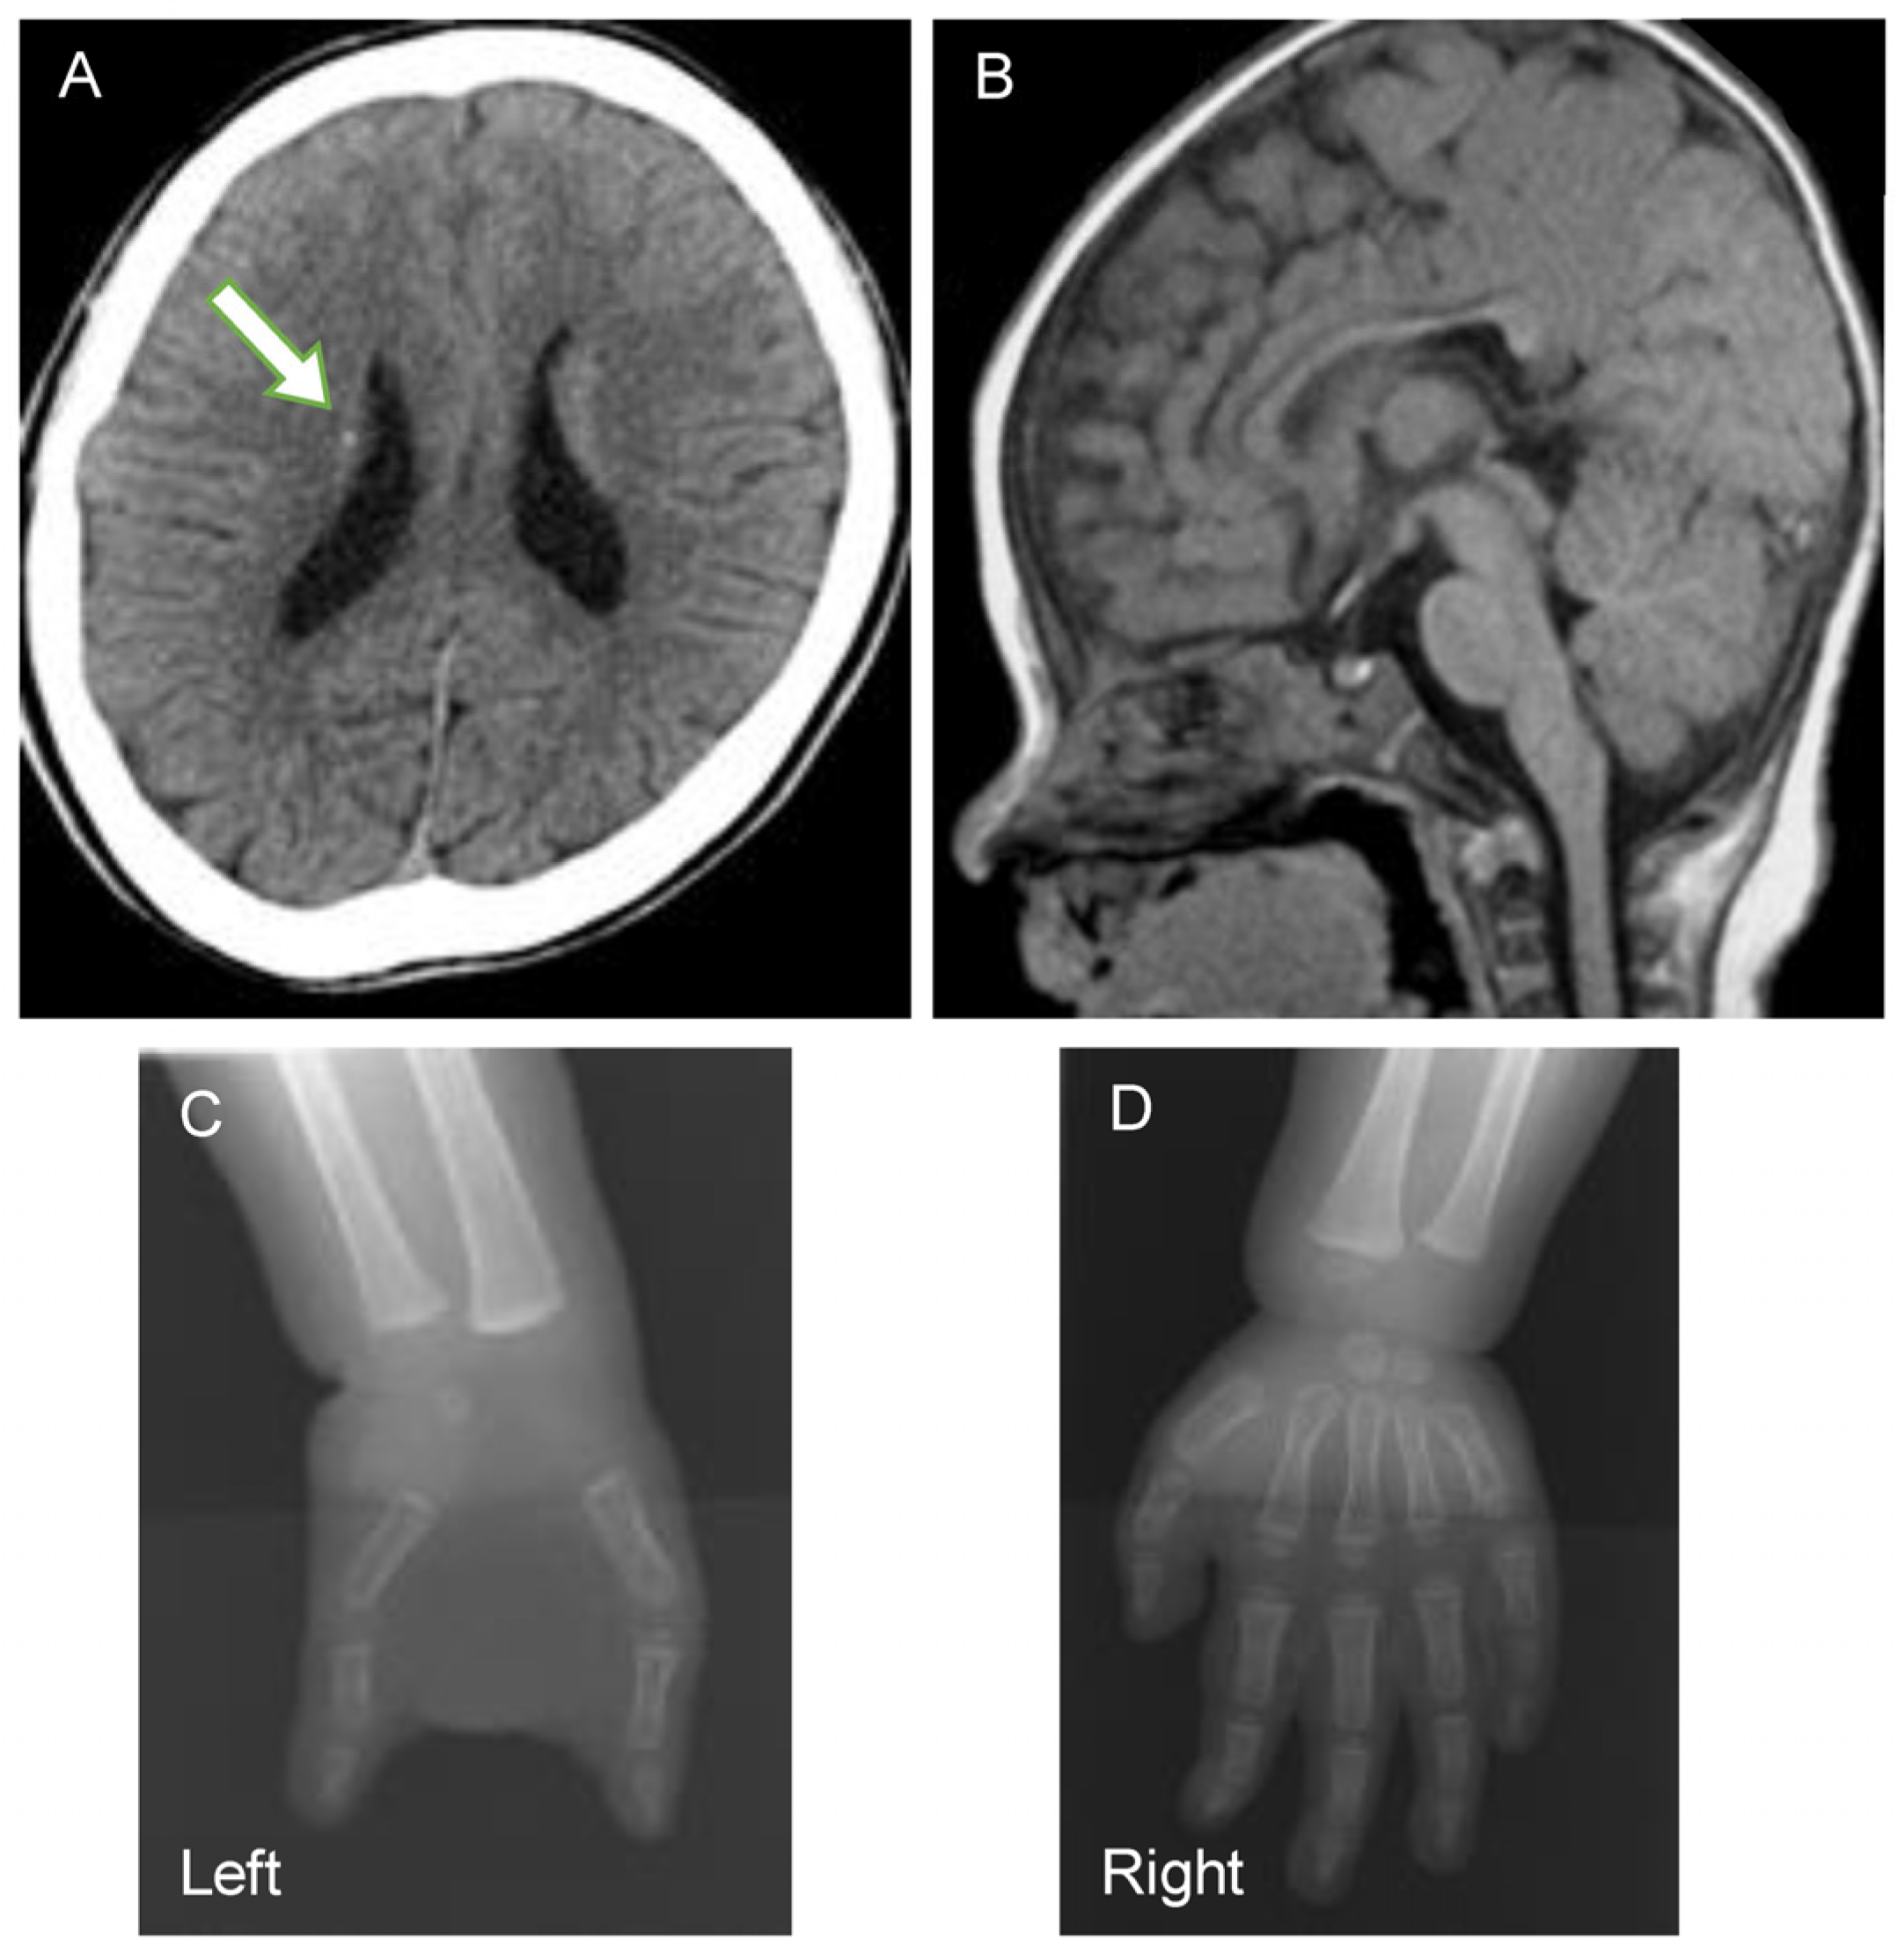

| 25 | F | 9/12 | DOCK6 | c.2786_2790dupAGCAC/ c.5154dupT | p.A931Sfs*11/ p.D1719* | Sporadic (AR) | 4/4 | ID, epilepsy, periventricular calcification, cerebral corpus callosum dysplasia, left 3-finger defect | This study |

| 26 | M | 4/12 | DOCK6 | c.4849G>A/ c.1292dupC | p.A1617T/ p.R431Pfs*9 | Sporadic (AR) | 4/4 | ID, epilepsy (West syndrome), periventricular calcification | This study |